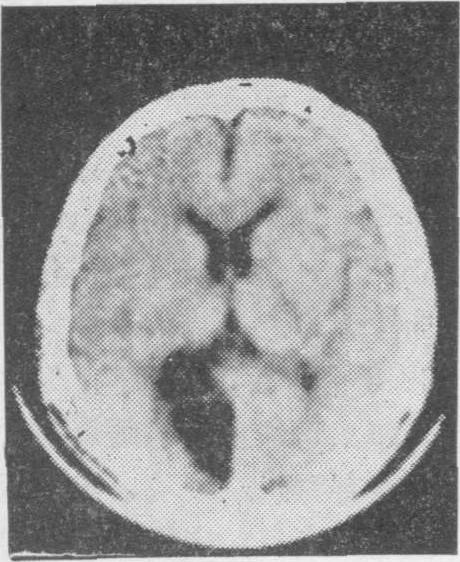

老年人脑血管病的诊断主要依靠详细询问病史,仔细观察临床症状和体征,并结合各种筛选检查。一般先用非创伤性检查,如脑电图、脑超声波、Doppler超声波、放射性核素脑扫描或计算机X线体层脑扫描检查等。特别是后者对老年人急性脑血管病的鉴别诊断更有帮助,可以鉴别是脑出血性病变(图3),脑缺血性病变(图4),抑或脑部肿瘤,以后根据需要再进行创伤性检查,如脑血管造影等。

图4脑缺血性病变的计算机X线体层脑扫描右侧枕叶有密度明显减低的缺血性病灶